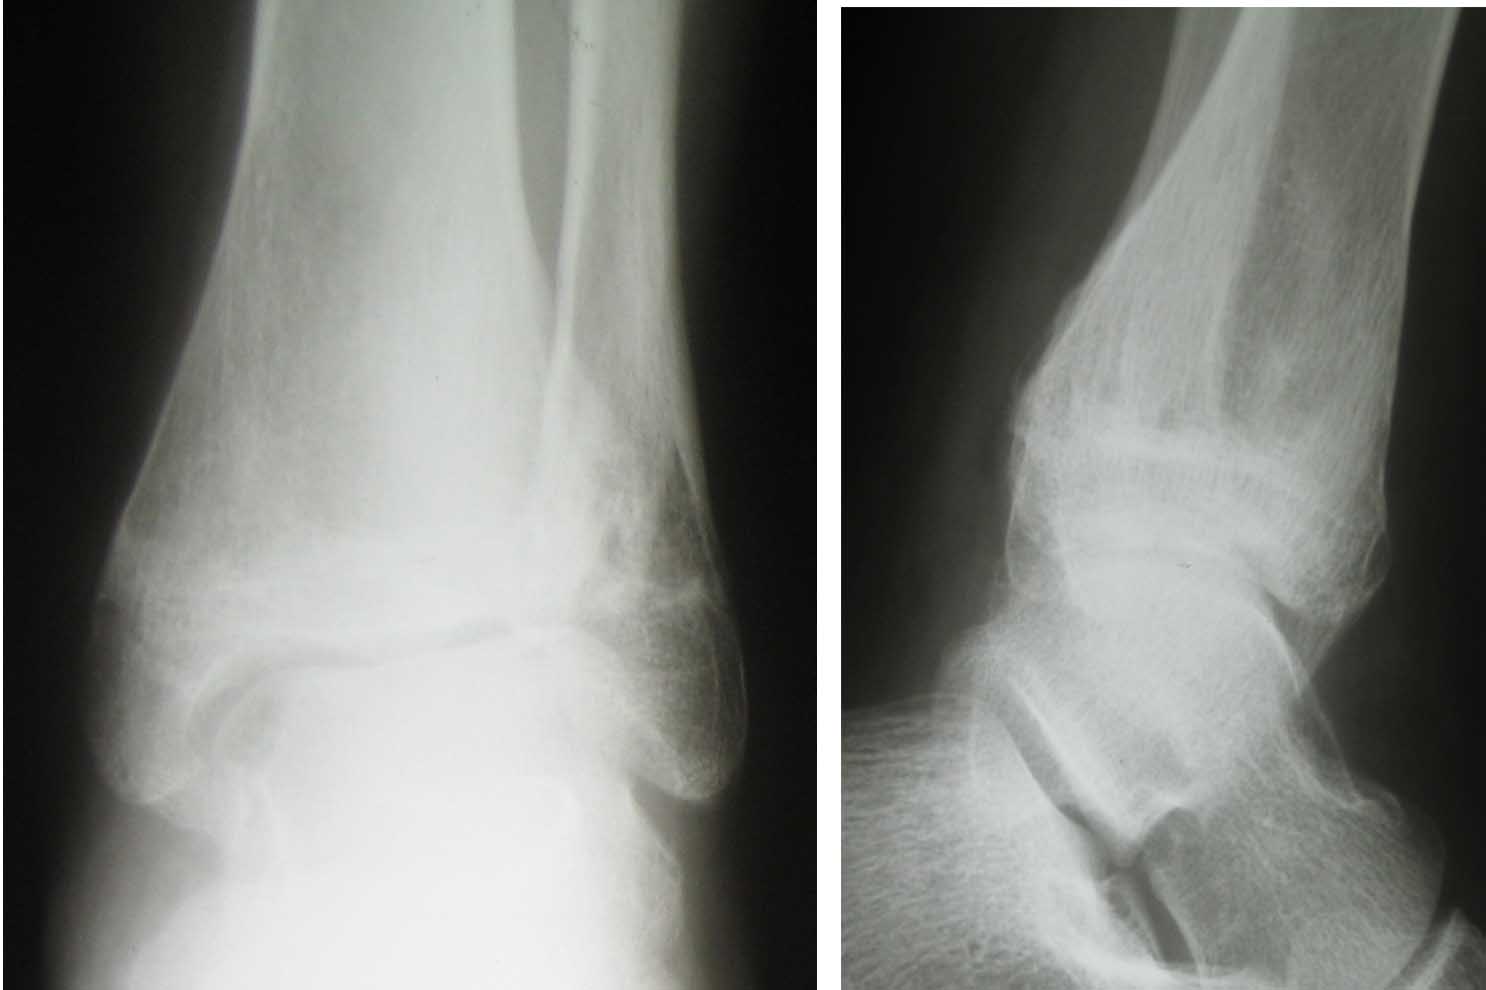

Вложение не в текстовом формате было извлечено…

Имя     : октябрь 2009.jpg

Тип     : image/jpeg

Размер  : 75003 байтов

Описание: отсутствует

Url     : http://weborto.net:8080/pipermail/ortho/attachments/20100123/d8a7ad29/attachment-0004.jpg

Имя     : январь 2010.jpg

Размер  : 65758 байтов

Url     : http://weborto.net:8080/pipermail/ortho/attachments/20100123/d8a7ad29/attachment-0005.jpg